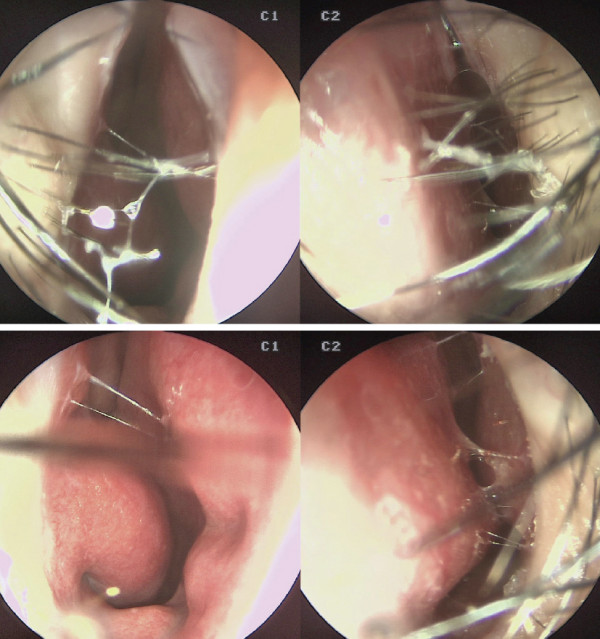

df19a8254135cde83df3de858f23ed04_1772171714_5054.jpg

선천적인 변형으로 인한 비밸브 협착도 발견되었다.

수술장 소견. 비중격의 만곡과 부분적인 결손이 관찰되었다. 좌측 상악부의 결손이 확인되었으며, 비중격 미단 하단부가 비가시(nasal spine) 좌측으로 휘어 있는 상태였다. 뼈 결손은 비가시의 좌측 부위와 비중격 골부에서도 일부 관찰되었다. 상대적으로 비중격 상단부 역시 좌측으로 만곡되어 있었다.